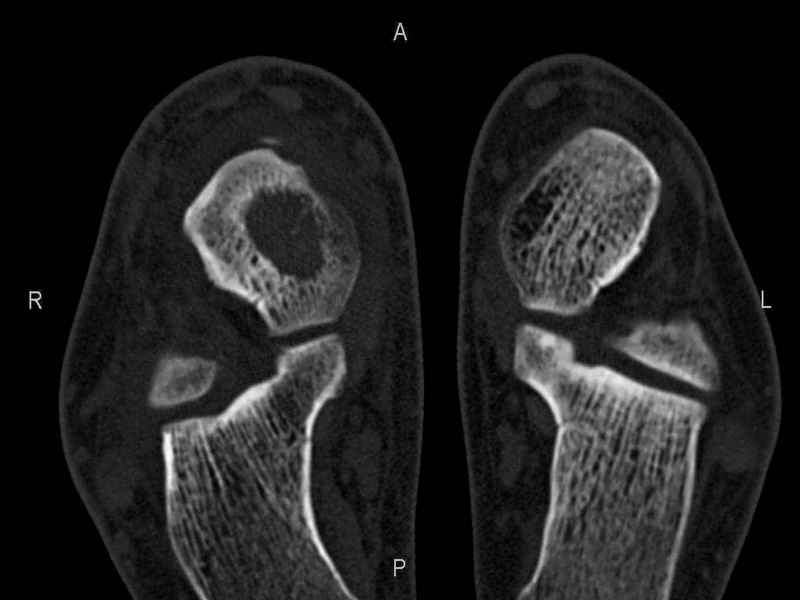

Уважаемые коллеги, обратился за помощью пациент, мужчина, 25 лет. С жалобами на болевой синдром в области голеностопного сустава и среднем отделе стопы. Травму отрицает. Со слов, болевой синдром в течении 1 года. Последние 1-1.5 мес периодически вынужден пользоваться костылями. После ограничения нагрузки боли уменьшаются.Соматически здоров. До появления болей активно занимался рукопашным боем. На СКТ картина рассекающего остеохондрита блока таранной кости, киста шейки таранной кости с признаками импрессии суставной поверхности. А также - разрастания переднего края б\берцовой кости сопровождающиеся клиникой импиджмент синдрома. Предполагаемый план лечения- удаление свободного фрагмента суставного хряща из трансмаллеолярного доступа с рассверливанием поверхности дефекта, кюретаж кисты шейки с заполнением полости биокомпозитом + дебридмент переднего отдела голеностопного сустава. Прошу высказать своё мнение, за и против, предполагаемого плана лечения. А также по возможности ответить на вопросы: 1. Есть ли необходимость в улучшении васкуляризации таранной кости (например подтаранный артродез). 2. Учитывая планируемое применение биокомпозитного цемента целесообразно ли заполнение им дефекта блока таранной кости с моделированием края суставной поверхности.

СТ чётко демонстрирует секвестр, но открыв сустав вероятно, что хрящ тарана окажется интактным и только пальпацией/ ЭОП можно будет

идентифицировать локализацию секвестра. Если вы с этим столкнетесь, то секвестрэктомию я бы предложил сделать не со стороны суставной поверхности тарана, а со стороны угла тарана, субхондрально кюрретаж стенок, разнонаправленную туннелизацию спицей или 1.1мм сверлом и заполнить дефект спонгиозным графтом.